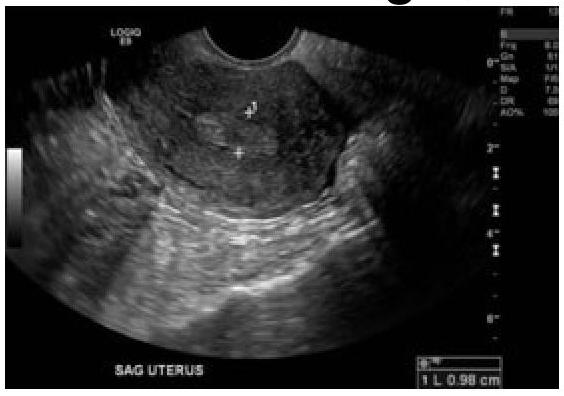

60-year-old female with a history of intermittent bleeding. What is the diagnosis based on the ultrasound image?

Explanation: ***Endometrial polyp*** - The ultrasound image shows a well-defined, **echogenic focal lesion within the endometrial cavity**, which is characteristic of an endometrial polyp. - In a 60-year-old female with intermittent bleeding, a polyp is a common cause of **postmenopausal bleeding** and is often identified as an intracavitary mass on ultrasound. - Endometrial polyps appear as **focal, hyperechoic or isoechoic masses** with a smooth contour projecting into the endometrial cavity. *Ca endometrium* - **Endometrial carcinoma** typically appears as diffuse endometrial thickening (>4-5 mm in postmenopausal women), irregular endometrial-myometrial interface, or heterogeneous endometrial echoes, often with evidence of myometrial invasion. - While bleeding is a cardinal symptom of endometrial carcinoma, the distinct **focal, well-circumscribed nature** of the lesion on ultrasound is less typical for carcinoma, which tends to be more diffuse and irregular. *Submucosal fibroid* - A **submucosal fibroid** (leiomyoma) is a benign smooth muscle tumor originating from the myometrium that protrudes into the endometrial cavity. - While it can appear as an intracavitary mass and cause abnormal bleeding, fibroids often have a more **heterogeneous or hypoechoic appearance** with posterior acoustic shadowing, compared to the isoechoic to hyperechoic appearance of a polyp. - The feeding vessel sign (blood flow at the base) is more characteristic of polyps than fibroids. *Endometrial hyperplasia* - **Endometrial hyperplasia** presents as **diffuse, uniform endometrial thickening** rather than a focal intracavitary mass. - It typically shows homogeneous increased echogenicity of the entire endometrium without a discrete, well-defined lesion as seen with a polyp. - While it can cause postmenopausal bleeding, the focal nature of the lesion in this case makes hyperplasia less likely.